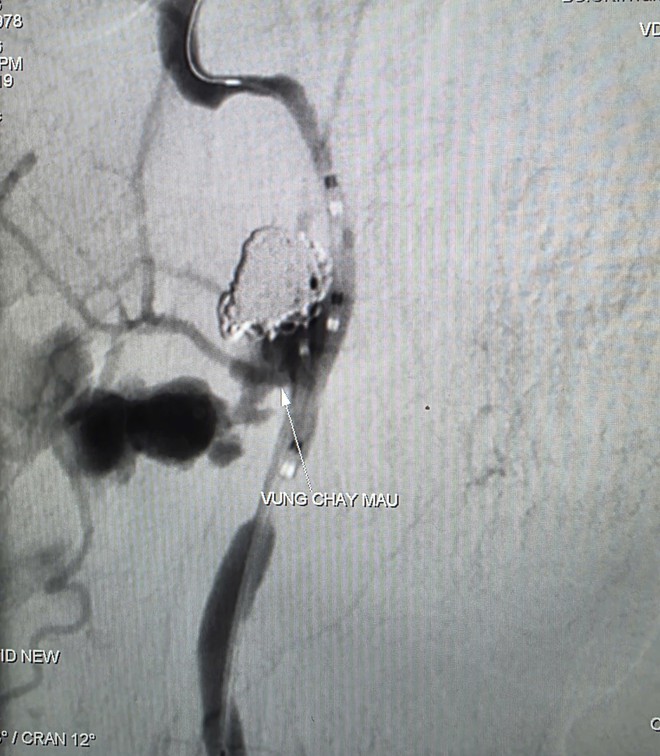

Hình ảnh thoát mạch trước và sau can thiệp. Ảnh: BVCC.

Các bác sĩ nhanh chóng tiến hành hồi sức tích cực, truyền máu khẩn và chỉ định chụp cắt lớp vi tính (CT Scan) có tiêm thuốc cản quang vùng hầu - mũi - họng để xác định nguyên nhân chảy máu. Kết quả chụp cho thấy một khối tổn thương vùng hầu lệch phải xâm lấn động mạch cảnh trong, kèm dấu hiệu thoát thuốc cản quang vào vùng hầu họng và hình ảnh giả phình động mạch cảnh trong đoạn dưới nền sọ, nguồn gây xuất huyết nghiêm trọng.

Kết quả chụp mạch ghi nhận ổ giả phình động mạch cảnh trong phải đoạn cổ, dưới nền sọ, kích thước khoảng 4,2 x 4,8 mm, cổ túi phình rộng và đang chảy máu. Ê kíp can thiệp đã sử dụng bóng để kiểm soát dòng chảy, sau đó đưa vi ống thông đến vị trí tổn thương và thả 9 vòng xoắn kim loại (coils) nhằm gây tắc hoàn toàn túi phình và đoạn động mạch cảnh trong phải, qua đó kiểm soát nguồn chảy máu.